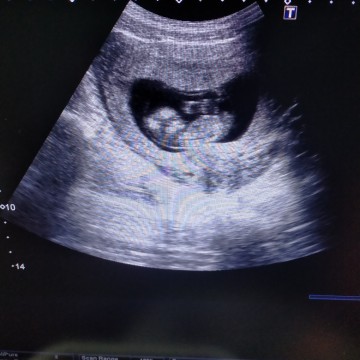

บ้านนี้ท้องแฝดกำหนดคลอดสิงหาคะ.. ยังมีอาการแพ้อยู่บ้าง.. บ้านอื่นเป็นงัยกันบ้างคร้า... เล่าสู่กันฟังบ้างสิคร้า#ทีมสิงหา